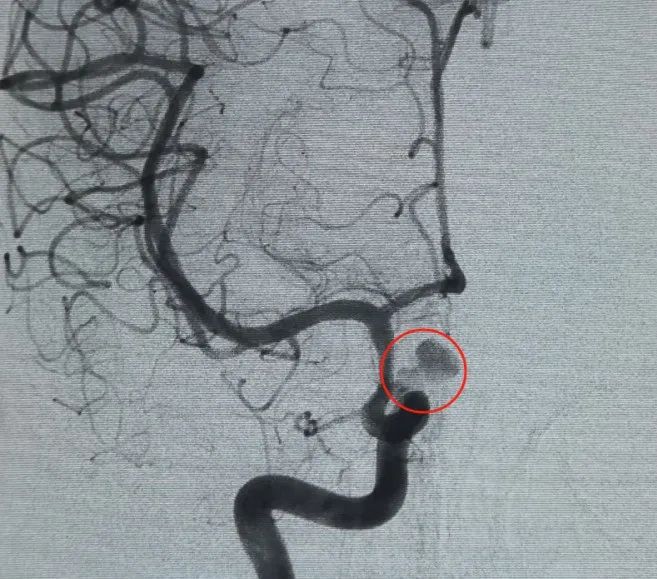

Diagnosis: Left internal carotid artery C6 segment ophthalmic artery aneurysm

Vascular access was established via femoral artery puncture, and a Perdenser® 6 mm × 20 cm 3D coil was first deployed to form a basket, achieving stable wall apposition and providing secure intrasaccular support. This was followed by the insertion of a Perdenser® 6 mm × 15 cm 3D coil to disrupt blood flow within the lobulated daughter sac.

A Perfiller® 3 mm × 6 cm expansible coil and a Perfiller® 3 mm × 2 cm expansible coil were then placed to complete neck occlusion. Subsequently, a Nuva® Flow Diverter (TJED-D-5.0-16) was delivered and deployed across the aneurysm neck. Follow-up angiography in both anteroposterior and lateral views confirmed excellent coverage, good wall apposition, and clear radiopacity, with marked contrast stagnation.